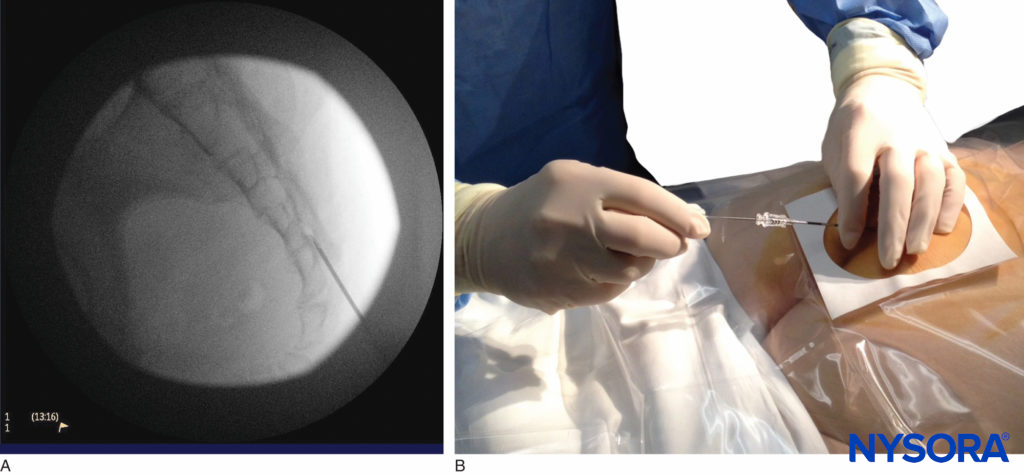

Once the tissues overlying the hiatus have been anesthetized, a 17- or 18-gauge Tuohy-type needle is inserted either in the midline or, using a lateral approach, into the caudal canal (Figure 5, Figure 6). A feeling of a slight “snap” may be appreciated when the advancing needle pierces the sacrococcygeal ligament. Once the needle reaches the ventral wall of the sacral canal, it is slowly withdrawn and reoriented, directing it more cranially (by depressing hub and advancing) for further insertion into the canal.

FIGURE 5. An 18-gauge, Tuohy-type needle is advanced from the skin into the sacral hiatus through the sacrococcygeal ligament. Usually, when fluoroscopy is not available to verify correct needle placement, a syringe loaded with air or saline is attached to the needle, and the loss-of-resistance technique is employed to identify the epidural space.

FIGURE 6. Lateral fluoroscopic image depicting the 18-gauge Tuohy needle correctly seated in the caudal epidural space.